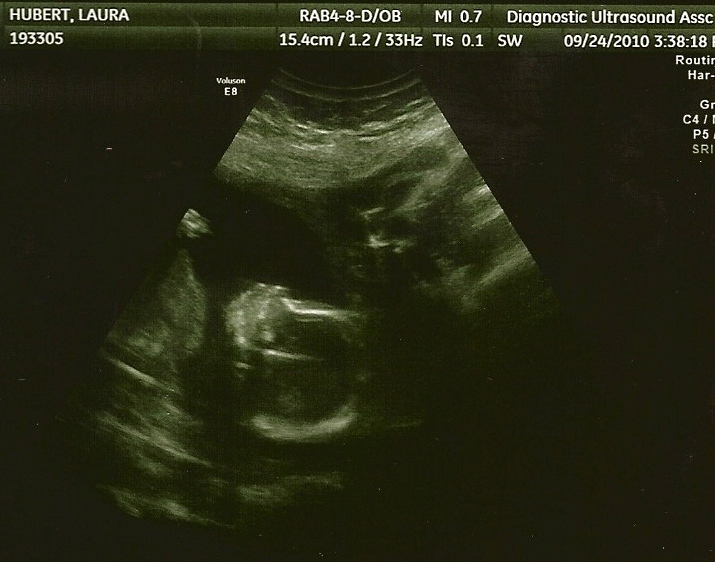

Ultrasound Pictures

18 weeks

9/24/10